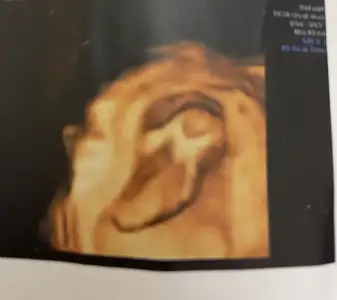

Ayy bende senin gibiyim aynı canım 13+3teyiz şuan aklım hep bebekte. Bir hareketlerini hissedebilseydikHaha mantıklı evet. Ama üç gündür iyi hissetmediğim için bebeği de merak ediyorumiçgüdüsel işte

Ayy bende senin gibiyim aynı canım 13+3teyiz şuan aklım hep bebekte. Bir hareketlerini hissedebilseydikHaha mantıklı evet. Ama üç gündür iyi hissetmediğim için bebeği de merak ediyorumiçgüdüsel işte